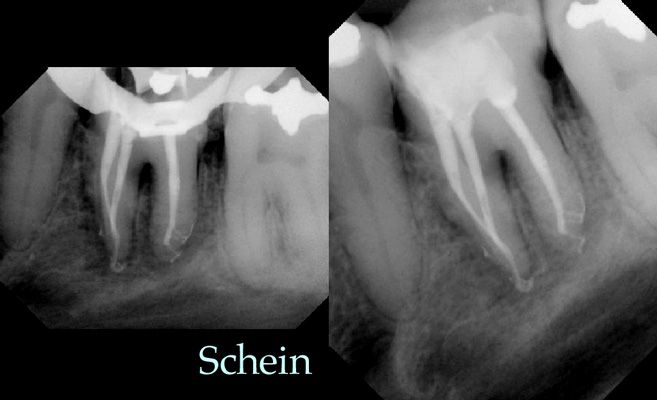

22